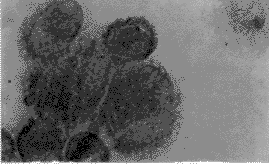

从大网膜消化下的原代HPMC细胞光镜下呈成串葡萄样,在培养瓶内初呈拉网状生长。融合后的细胞呈多边形,边缘不齐,形成铺路鹅卵石样外观(图1)。瑞士姬姆萨染色后胞浆为淡粉色,中央为深蓝色扁圆形核,细胞计数纯度可达95%以上(图2)。ABC法细胞免疫组化染色分析发现,细胞角蛋白、波形蛋白抗原阳性(图3、4),第Ⅷ因子相关抗原和白细胞CD45抗原阴性。根据细胞表面抗原标志分析染色结果,可排除成纤维细胞(细胞角蛋白阴性、波形蛋白抗原阳性)、内皮细胞(第Ⅷ因子相关抗原阳性)或白细胞(白细胞CD45抗原阳性)的可能,证实分离培养的是腹膜间皮细胞。

图1 光镜下细胞呈多边形,形成鹅卵石样外观

Fig.1 Cobblestone-like appearance of the confluent cells under microscope. ×125